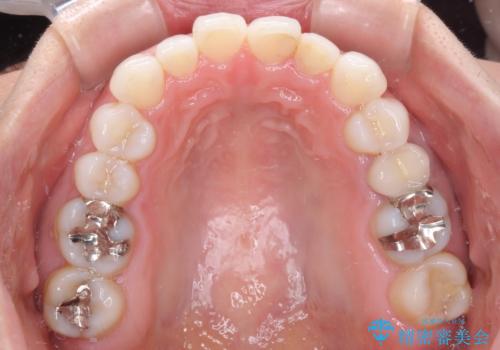

軽度の叢生をインビザライン・ライトで解消

- 前歯が気になるとのことで来院された患者様です。

歯列不正は軽微であったため、インビザライン・ライトにより、費用を抑えて矯正治療を行うこととしました。

短期間で気になる前歯の歯列を改善することができました。